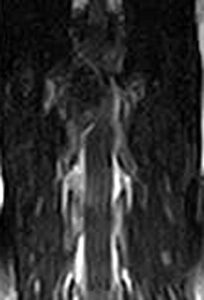

市内の先生からダックスちゃん両後肢麻痺グレード3でMRI検査及び手術依頼でご紹介がありました。MRI検査で第12‐13胸 椎間椎間椎間板ヘルニア、右側優位な圧迫と診断し即日手術となりました。→<その2>へ続く